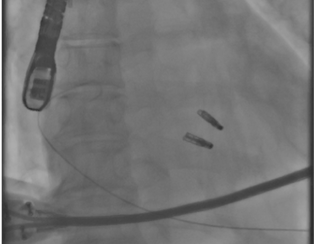

- 僧帽弁逆流が最大限消失する場所への弁尖把持が何度でも施行可能

- 外科的介入を温存することができる